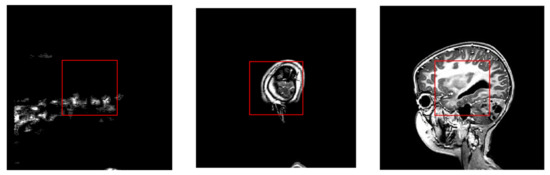

- Recognition of Video Content:

- Frontal Plane: The model could not clearly recognize the medical context, suggesting motion and contour analysis;

- Sagittal Plane: The model suggested a medical imaging context and tumor detection based on context and image analysis.

- In the frontal plane, potential tumor regions are marked with green contours. In the sagittal plane, potential tumor regions are marked with red rectangles;